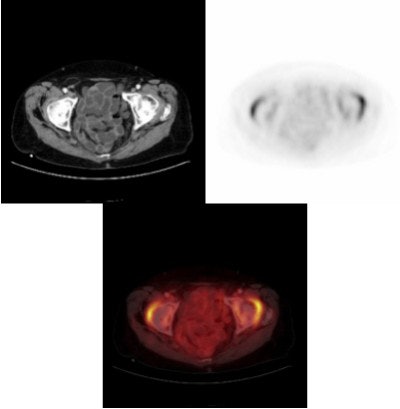

![]() |

| When applying a negative oral contrast agent such as a locust bean gum/mannitol solution, there is homogeneous tracer distribution on both PET (right) and PET/CT (bottom). (Note the glucose uptake in the area of both hips, most probably due to inflammatory reaction.) Image and caption courtesy of Dr. Gerald Antoch, department of radiology at University Hospital of Essen. |